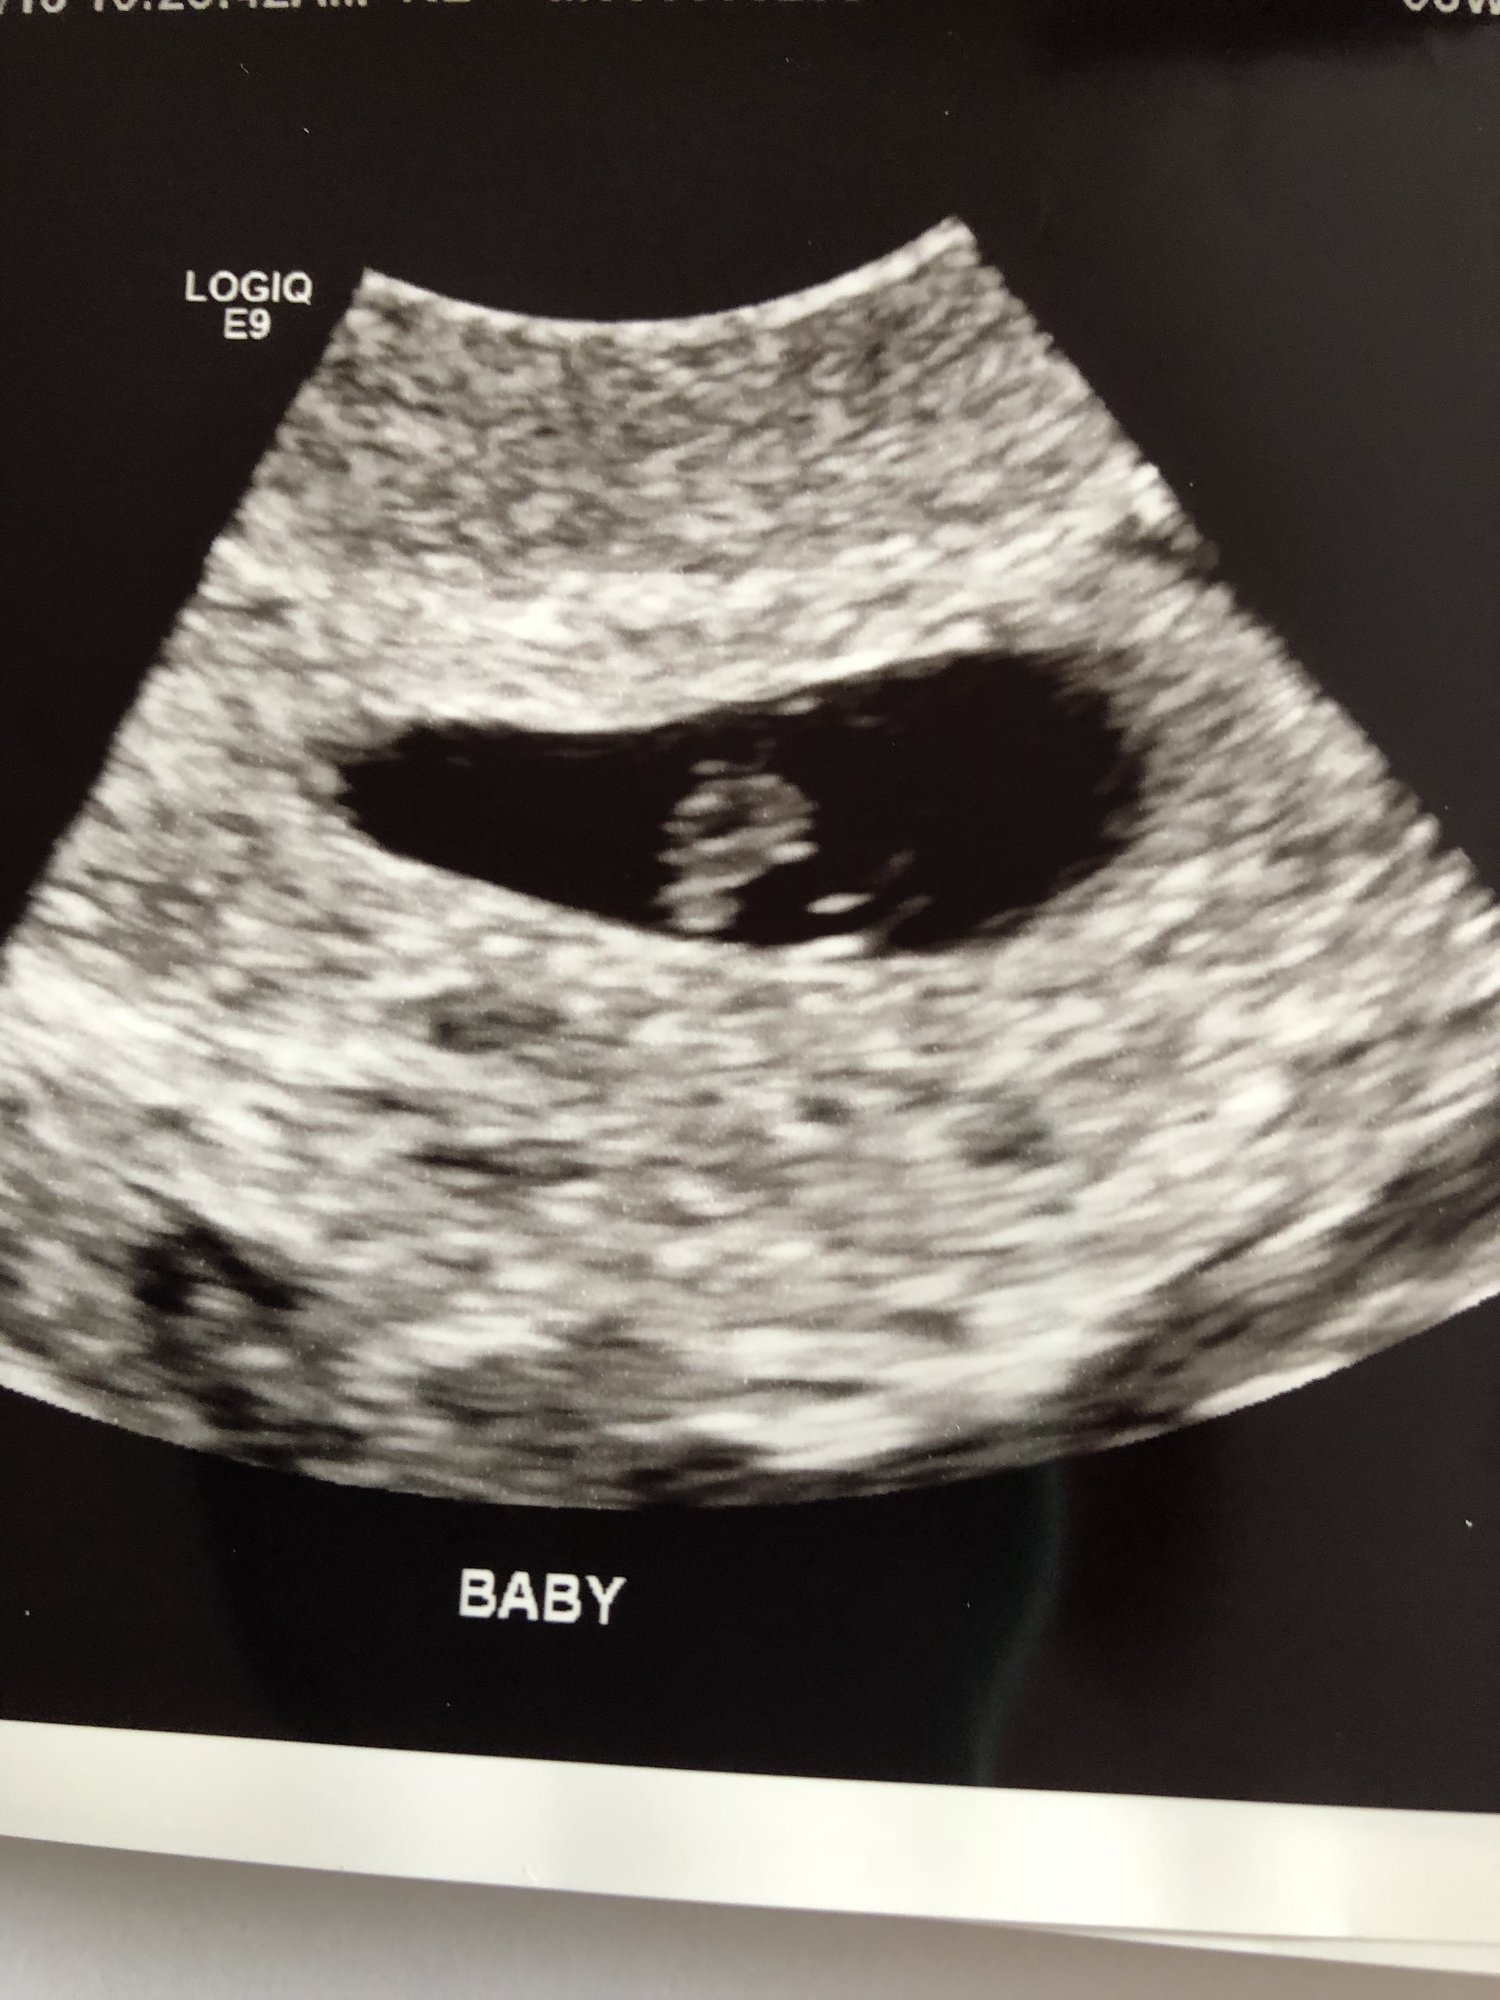

had my first appointment and viability scan today. Knew pretty quickly with how the tech and np were acting it wasn’t good. I’m measuring 2 weeks behind at 6w and heartbeat is only 50. I go back in a week for a follow up ultrasound and check in unless I miscarry naturally or decide to go ahead with procedure before then. I’m so torn on what to do. There is a heartbeat and I don’t want to be the one to decide to end that, but I also just want it to be over with. I hope that doesn’t sound horrible. Here is a picture of my little love.